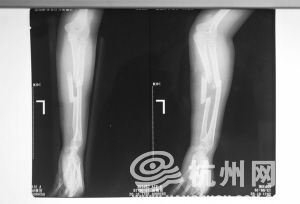

吴菊萍左手臂尺桡骨断成了三截